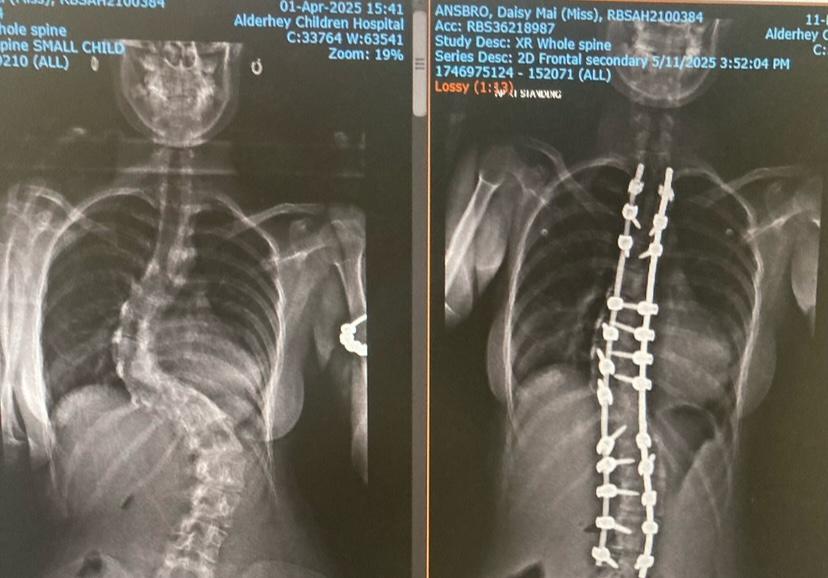

Daisy Mai had been diagnosed with scoliosis as a baby and monitored closely throughout childhood.

In May 2025, she underwent a complex nine-hour posterior spinal fusion.

During the surgery, surgeons inserted two rods and 22 screws to straighten and stabilise her spine, along with a costoplasty procedure that involved removing two ribs to help reshape her rib cage.

The results have been remarkable.